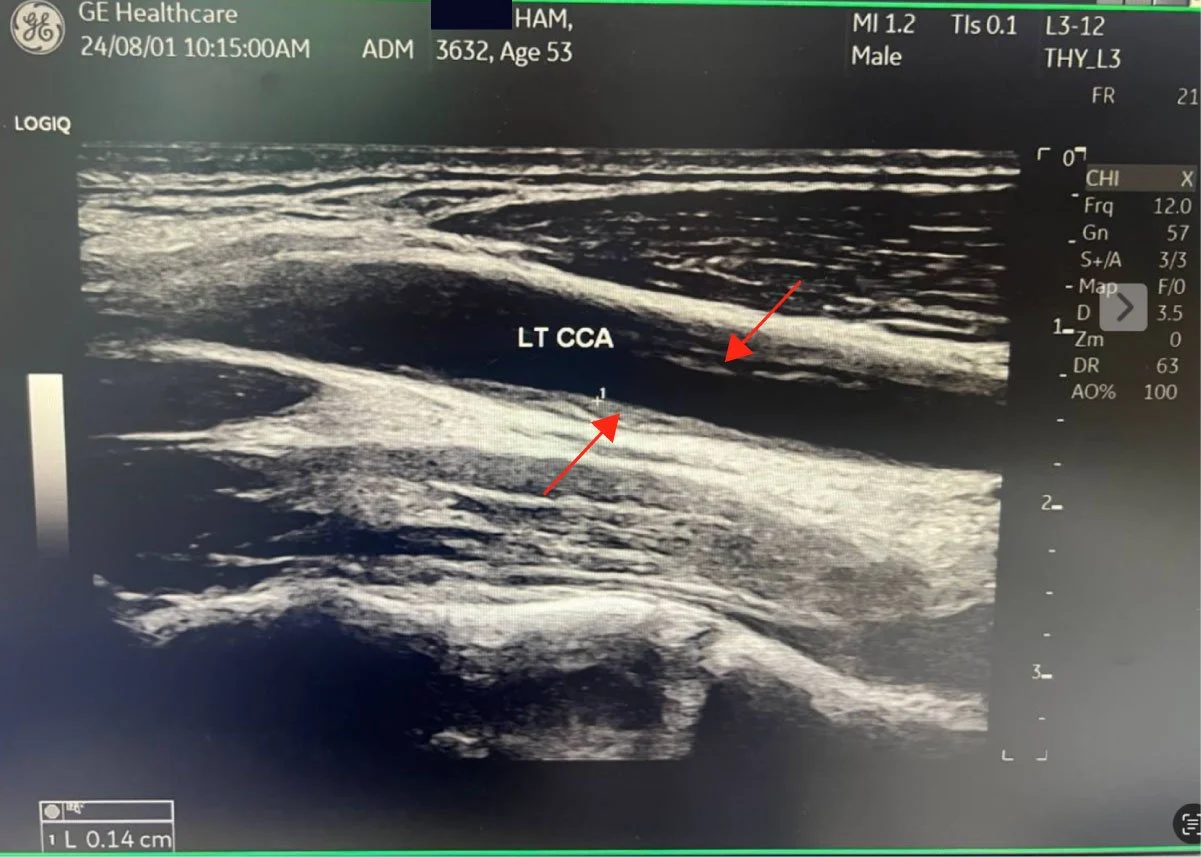

As you may know, I had bilateral plaque in the carotid arteries, now all gone. It seems almost miraculous, so I am studying the studies to understand the mechanism of how and what happened for such a remarkable result. I have reviewed the major carotid artery studies on exercise.

After thinking how I reversed my carotid plaque from May 9, 2025 (Started WFPB Esselstyn diet) to August 19, 2025, when my carotid ultrasound showed that all my plaque was gone and CIMT reduced 53%, I have been trying to understand the mechanism and biochemical pathways this occurred. I have been so focused on diet, that I wondered how much my 3000 km of cycling played a role. I did three Gran Fondo (120+ km) rides last year. Then after my September fondo, I basically stopped riding. My coronary plaque did not really reverse after that, although blood flow improved remarkably. So that has made me curious.

The carotid ultrasound at three months showed something I had hoped for but had not been certain enough to expect: both carotid arteries were completely clear. Not reduced. Clear. The plaques had resolved bilaterally in just three months. And the CIMT, the intima-media thickness that had read like an 85-year-old when I started, crossed into high-normal for age 55. By month ten, it was mid-normal. A 53% bilateral reduction in carotid arterial wall thickness, confirmed on imaging another three times afterwards, always improving.